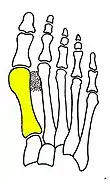

Cerclage bone sutures

Fig. 2: Cerclage bone sutures

Syndesmosis procedure addresses specifically the two fundamental problems of metatarsus primus varus deformity that gives rise to the bunion deformity. They are leaning and instability of the first metatarsal bone . Syndesmosis procedure uprights the leaning first metatarsal bone with strong binding sutures between it and the second metatarsal bone (Fig. 2) and then also stabilizes it uniquely by creating a fibrous connecting bridge between these two bones (Fig. 3, 4). First metatarsal bone can be readily realigned because by definition of the metatarsus primus varus deformity its first metatarsal is abnormally loose and mobile.